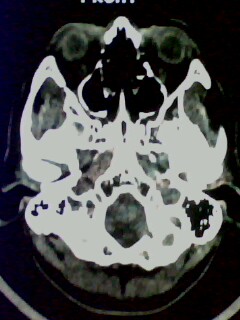

以下是引用随光逐影在2009-5-20 19:22:00的发言:[br]1)考虑左上颌骨近中线区含牙囊肿。2)鼻中隔右突偏曲。3)双侧下鼻甲肥大。

以下是引用余辉在2009-5-20 19:35:00的发言:[br]1)考虑左上颌骨近中线区含牙囊肿。2)鼻中隔右突偏曲。3)双侧下鼻甲肥大。[br]支持,不除外上颌骨正中囊肿,有窦道通鼻前庭,出血可能是内部有感染,图像不是很清,可照个片看一下